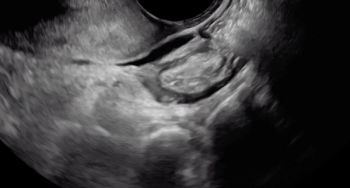

Large rectal deep endometriosis nodule completely fixed to the fundus of a retroverted, retroflexed uterus, resulting in complete rectouterine pouch obliteration (negative sliding sign).

Viewers should focus their eyes on the area closest to the probe, the vagina. With the application of pressure, the operator is attempting to understand whether the bowel is tethered, which it is (demonstrated by the acute angle of the rectal wall muscularis being pulled toward the area of the deep endometriosis nodule).